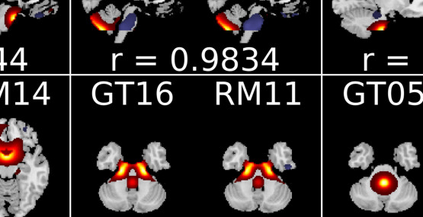

In the last two decades, unsupervised latent variable models---blind source separation (BSS) especially---have enjoyed a strong reputation for the interpretable features they produce. Seldom do these models combine the rich diversity of information available in multiple datasets. Multidatasets, on the other hand, yield joint solutions otherwise unavailable in isolation, with a potential for pivotal insights into complex systems. To take advantage of the complex multidimensional subspace structures that capture underlying modes of shared and unique variability across and within datasets, we present a direct, principled approach to multidataset combination. We design a new method called multidataset independent subspace analysis (MISA) that leverages joint information from multiple heterogeneous datasets in a flexible and synergistic fashion. Methodological innovations exploiting the Kotz distribution for subspace modeling in conjunction with a novel combinatorial optimization for evasion of local minima enable MISA to produce a robust generalization of independent component analysis (ICA), independent vector analysis (IVA), and independent subspace analysis (ISA) in a single unified model. We highlight the utility of MISA for multimodal information fusion, including sample-poor regimes and low signal-to-noise ratio scenarios, promoting novel applications in both unimodal and multimodal brain imaging data.